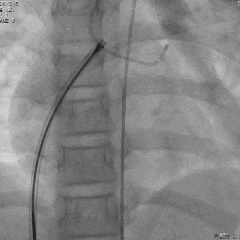

封堵器锁定后造影

封堵器锁定后造影,封堵器位置正确,瘘管封堵完全,右心房无造影剂显影